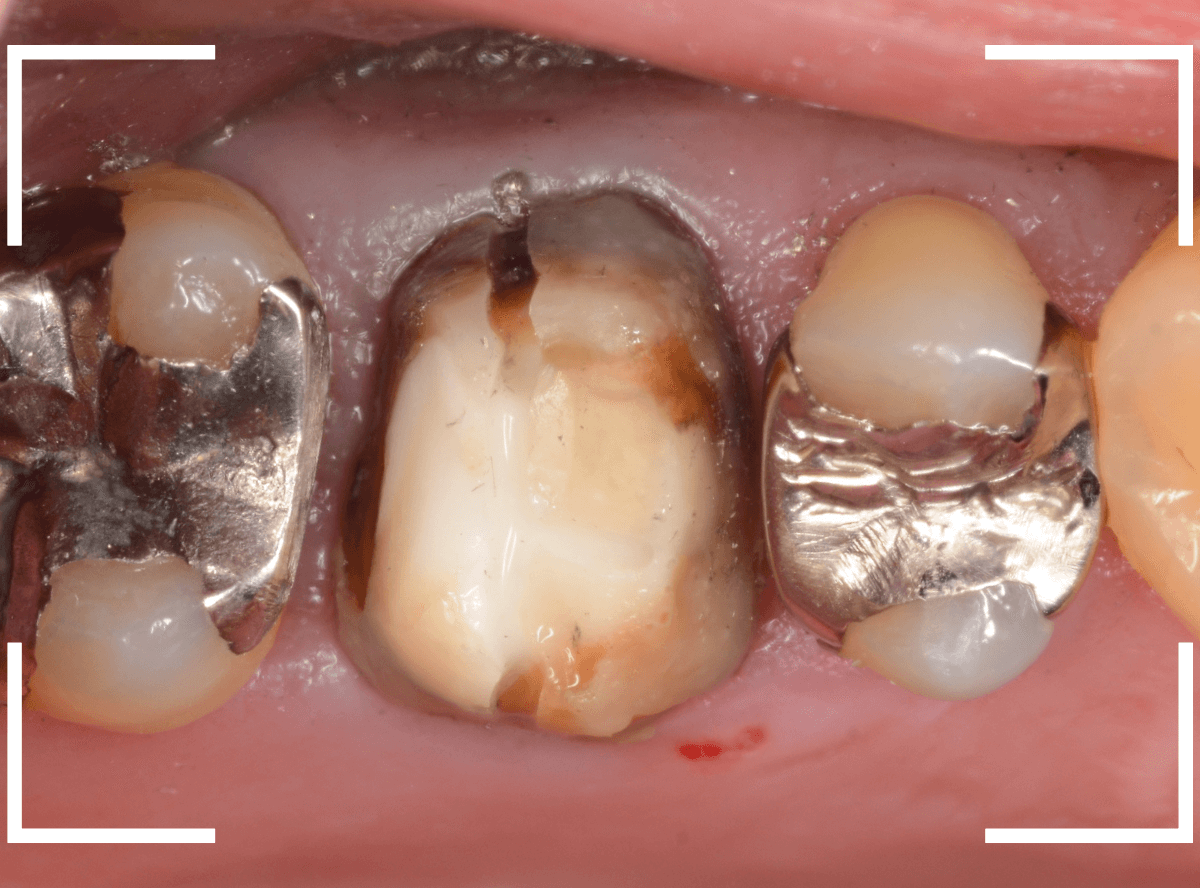

Case.20 メタル・インレーとメタル・クラウンをジルコニアにやり替え

「下の奥歯の銀歯を白くしたい」というご希望の患者さんです。

メタル・インレーとメタル・クラウンが入っていますね。

まずは、奥のメタル・クラウンを外します。

メタル・コアが入っていますが、こちらも慎重に外して、中を調べていきます。

レントゲン写真では問題なさそうでしたが、メタルコアを除去すると、中は真っ黒でした。

このように、コアの中で虫歯が進行している場合もありますので、さし歯をやり直す際は、出来る限りコアも外して調べるようにしています。

虫歯を全て除去しました。

幸い、あまり多く削る事なく進められたので良かったです。

手前の歯のつめ物も外します。

こちらもお薬が入っていますが、外して中を調べます。

こちらは中も問題なかったです。